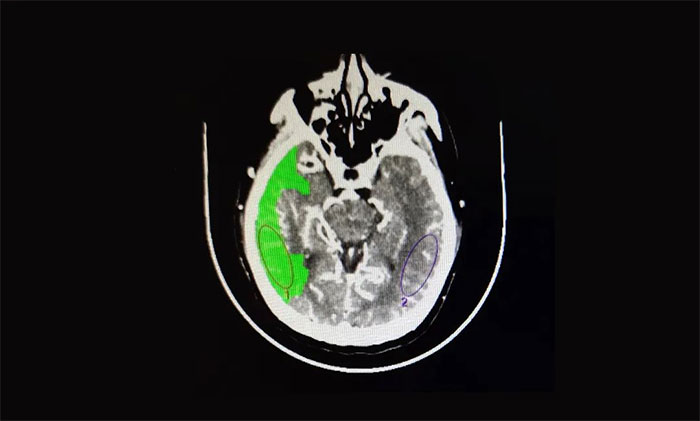

醫(yī)院腦血管病病區(qū)主任張琪博士指出,患者從癥狀上看考慮急性大血管閉塞。急診頭顱CT平掃提示:右側(cè)枕頂葉低密度灶;頭顱CTA提示:右側(cè)大腦中動脈M1段節(jié)段型重度狹窄;頭顱CTP:右側(cè)大腦半球腦組織灌注不足,存在缺血半暗帶。

▲ CTA提示:右側(cè)大腦中動脈M1段節(jié)段型重度狹窄

▲ 頭顱CTP:右側(cè)大腦半球腦組織灌注不足

綜合患者病史和影像檢查,診斷為:急性腦梗死(右側(cè)大腦中動脈閉塞),如果不做手術,患者右側(cè)大腦半球?qū)⒋竺娣e腦梗死,死亡率極高,病情十分兇險。在跟家屬溝通并征得同意后,張琪博士決定為其實施血管內(nèi)介入治療。